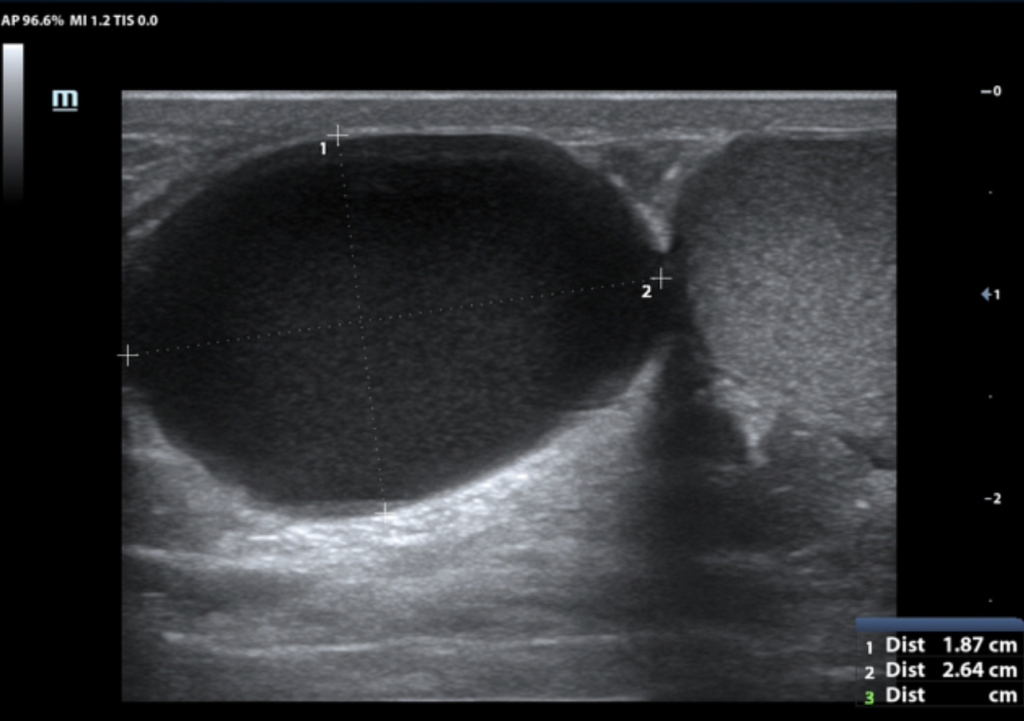

Hydrocele – anechoic fluid (F) surrounding testis (T).

- Findings: A hydrocele appears as an anechoic fluid collection between the parietal and visceral layers of the tunica vaginalis, and can contain low-level echogenic foci if proteinaceous or infected.

- Note: Hydroceles are either primary, due to incomplete closure of the processus vaginalis, or secondary, caused by infection, trauma, or malignancy.